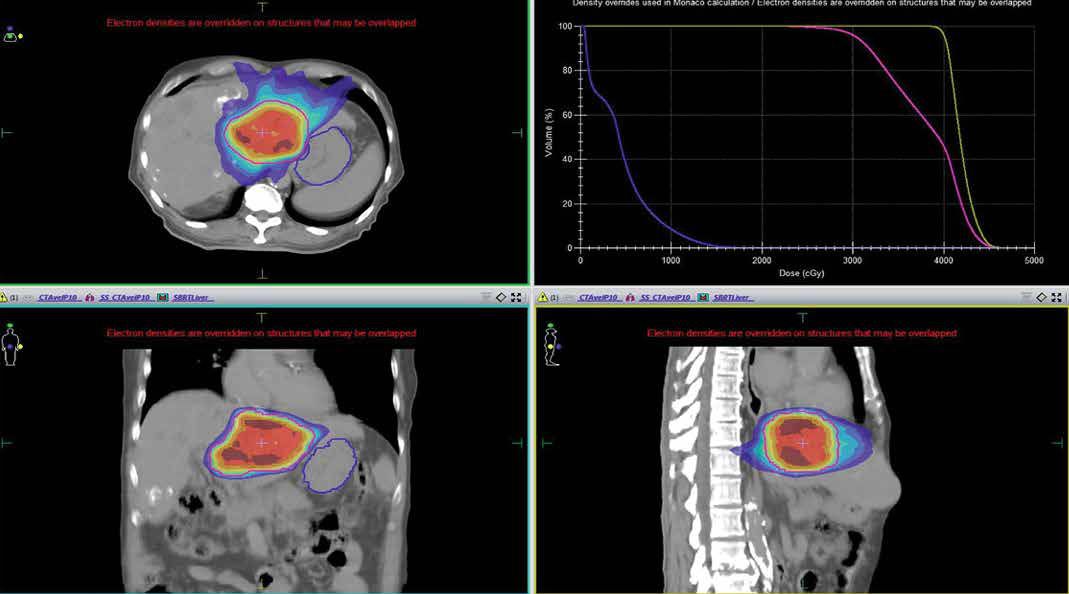

SBRT delivers highly focused and potent radiation doses to the tumour site with remarkable precision. This advanced approach involves sub-millimetre accuracy, enabling the delivery of intense radiation within a short timeframe, typically spanning just a few sessions over one to two weeks. This is in stark contrast to the extended daily external beam radiation treatment that spans several weeks.

Suitable for small and well-localised tumours located in critical or challenging areas, such as the lungs, liver, or spine.

SBRT is characterised by hypofractionation, where the total prescribed dose is delivered in a small number of fractions (typically 1 to 5 fractions).

Delivers very high doses of radiation in each session.